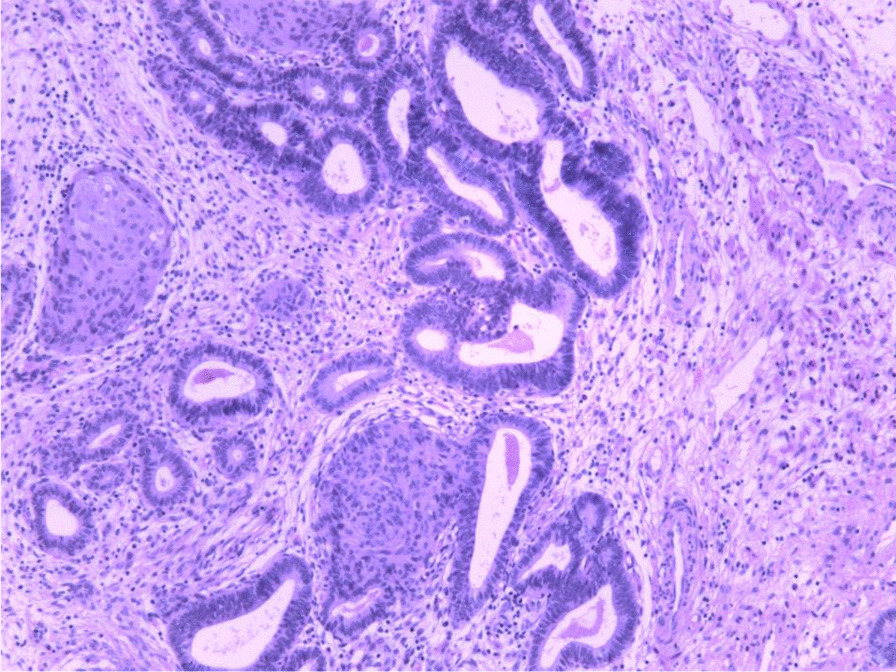

Pathological diagnosis

APA was diagnosed pathologically after hysteroscopic resection of the lesion (Fig. 2). According to the degree of abnormality of the APA surface glands, APA was classified as APA-L or APA-H [11]. More than 30% of the APA surface glands had complex structures characterized by branching and budding (Fig. 2), in which dense glands coexisted with branched glandular duct structures. There were 36 cases of APA-L and 8 cases of APA-H. Hysteroscopic biopsy of the endometrium in other parts of the uterine cavity revealed mild or moderate atypical hyperplasia in 7 patients.

Fig. 2.

Representative microscopic appearance of atypical polypoid adenomyoma (H&E stain)